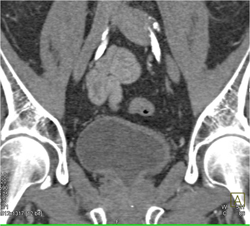

Bladder Cancer